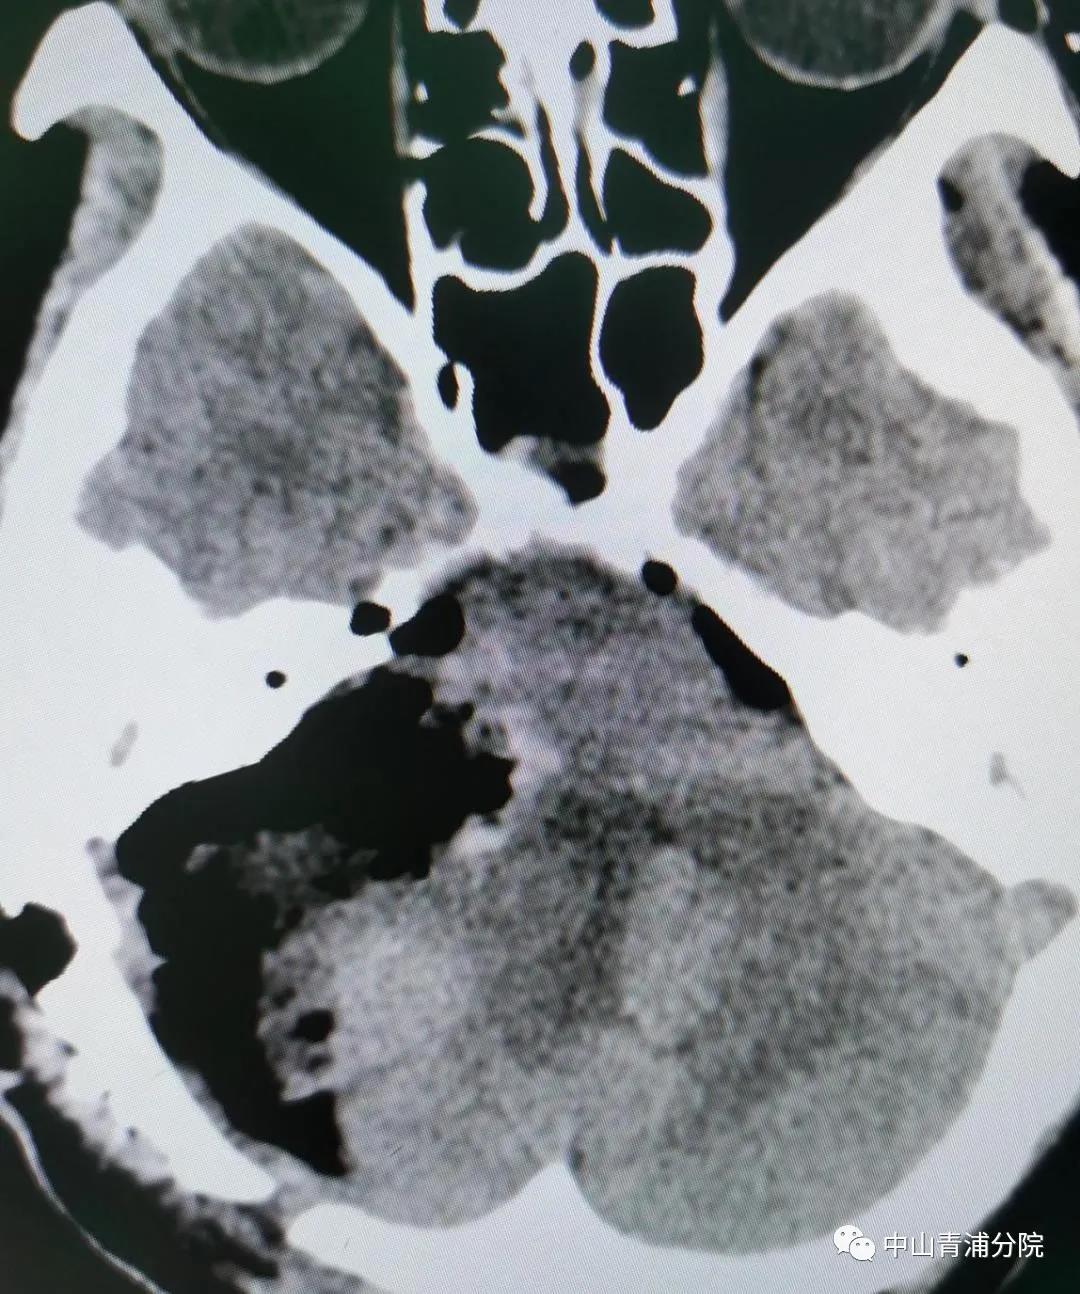

李季林副主任医师团队请来麻醉科蒋晖主任会诊,从手术方案、突发情况应对、麻醉风险预案等等方面反复推敲探讨,形成最佳治疗方案。2月19日,在麻醉科的全力协助下,一台“听神经病损切除术”正在紧张进行。虽说分离神经如履薄冰,但胆大心细、技术娴熟的神经外科医生团队怀着对生命的敬畏,对职业的信念,有条不紊地进行着。

(第三次术后CT)

手术成功!张阿姨术后恢复良好,于3月8日康复出院。